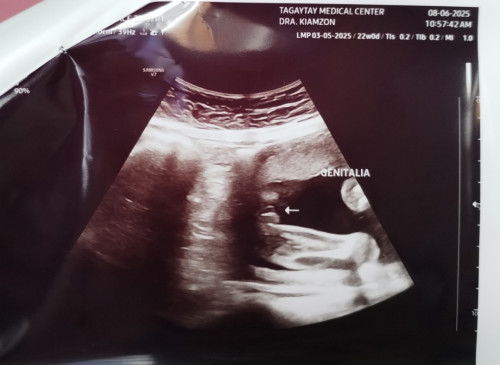

Is this a boy or girl?

girl po basta hamburger shape..๐ค

Girl, parang hamburger ang shape eh

parang hamburger nga. it's a girl ๐

girl๐ halata yung ping ping๐

baby girl ๐ฉท๐ฅฐ